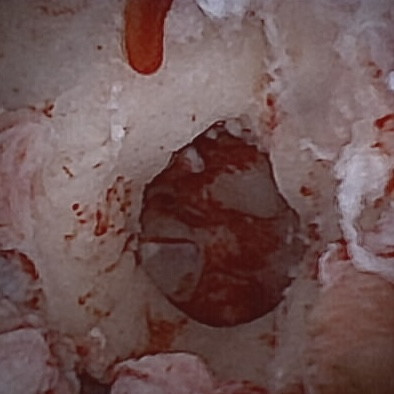

Trois cas résultent de l'extension d'une otite. Ces patients étaient présentés pour ataxie et l'un d'entre eux présentait également des crises convulsives partielles. Dans les trois cas, un examen scanner a mis en évidence une otite moyenne associée à une lésion intracrânienne extra-axiale adjacente, évoquant un empyème méningé. Dans le premier cas, un traitement antibiotique probabiliste permet la résolution des signes cliniques. Dans le deuxième cas, des prélèvements par vidéo-otoscopie permet d'identifier la présence de Staphylococcus felis. Un traitement antibiotique ciblé entraîne la résolution des signes cliniques. Dans le troisième cas, l'examen vidéo-otoscopique permet l'identification de Pseudomonas spp. Malgré une antibiothérapie adaptée, l'état clinique du patient se détériore. Un nouvel examen scanner montre une aggravation de l'empyème méningé. Une craniotomie est réalisée et permet le débridement de l'empyème. Cette intervention, associée à une corticothérapie et la poursuite de l'antibiothérapie, permettent la résolution des signes cliniques.